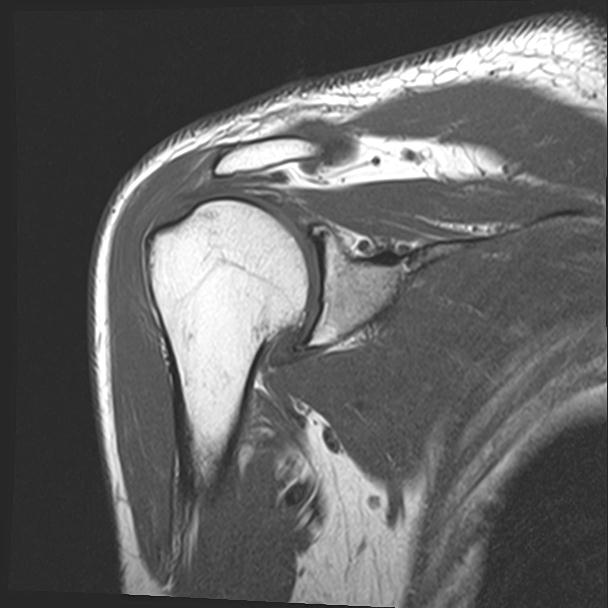

60058 3/9 11/4 右肩 2R+MRI 73歳男性 肩腱板損傷